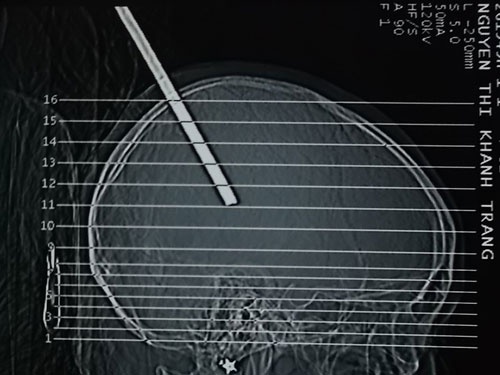

Bị xà beng đâm xuyên qua đầu nhưng anh Phạm Văn Tú đã được các y bác sĩ bệnh viện đa khoa Đà Nẵng cứu sống.

Rất may, anh Tú được đưa đi cấp cứu kịp thời và sau hơn 1 giờ phẫu thuật, anh đã thoát khỏi cơn nguy kịch.

Ca mổ được tiến hành trong suốt 3 giờ. Khi rút cây sắt ra, mô não phòi ra một khối kích thước cỡ 3x4cm.